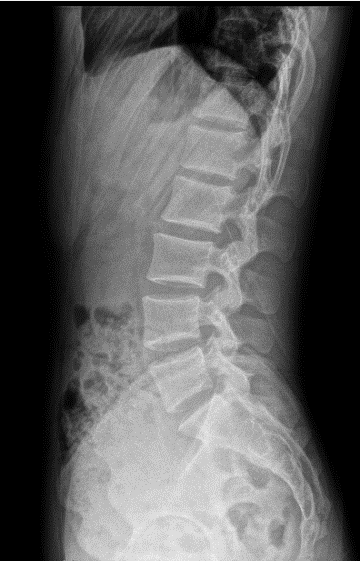

全自动全景成像(选配)

三次点击,两个步骤,一气呵成

全过程一分钟内完成,摄影条件智能设定,根据不同体厚智能曝光补偿,宽幅窄缝按需选择,无需往返机房调整机架位置,一气呵成自动全景成像